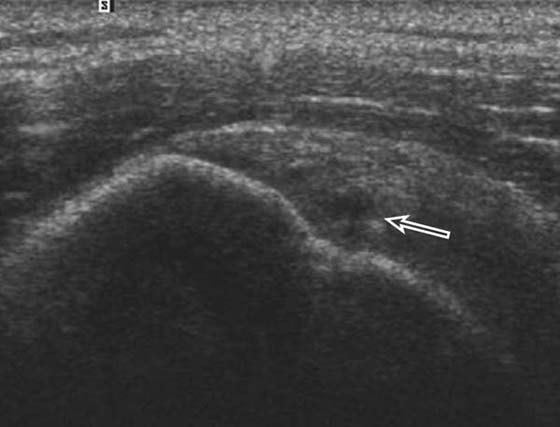

US is also a valuable tool in the assessment of impingement18 and is useful for the evaluation of rotator cuff pathology (Fig. 14-8) although it cannot give a global assessment including labral, capsular, cartilage, and marrow pathology. US is useful in the setting of rotator cuff repair and is particularly useful in shoulder arthroplasty where susceptibility artifact from the metallic prosthesis on MRI would limit interpretation of the adjacent cuff.19 In addition, calcific tendinosis of the rotator cuff is well demonstrated on US20 and is often amenable to SASD bursal injection of steroid and anesthetic or needling in refractory cases.

images

Figure 14-8 Partial-thickness rotator cuff tear. Ultrasound along the long axis of the distal supraspinatus tendon adjacent to its insertion on the greater tuberosity demonstrates a focal partial undersurface tear (arrow) as indicated by a hypoechoic (dark) defect.